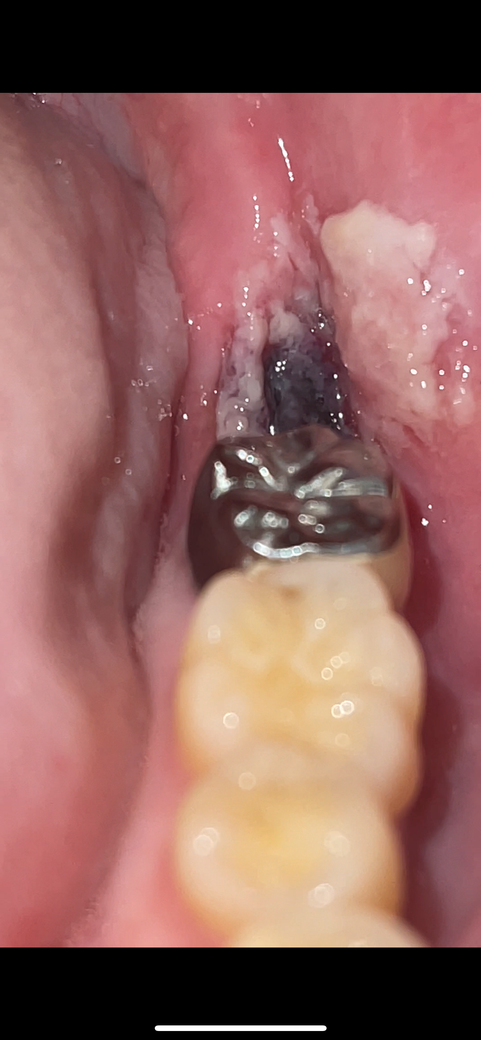

사랑니 4일차 혈병이 떨어지려는 것처럼 보이는데 괜찮나요?

사랑니 발치 4일차인데 뿌리가 안쪽 ㄱ자로 휘어진 기형인 사랑니를 발치했습니다.

크게 고생할거라 하셨지만 지혈은 8시간이 돼서야 되었지만 그래도 큰 고통없이 혈병이 형성됐습니다

그런데 3일차부터 호빵,자장면 등 일반식을 섭취하기 시작했는데

4일차인 오늘 혈병 쪽에 욱씬거리는 통증과 함께 떨어지려는 것처럼 보이는 현재 상태가 되었습니다

• 2번 째 사진